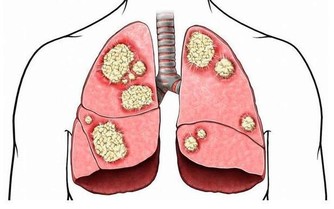

小的時候,正處於生長發育的關鍵時期,所以家人總會讓吃很多東西,但是中年人則不能再這樣肆無忌憚地吃了。一方面中年人容易長膘,另一方面中年人的器官功能開始下降,那麼為了預防生病,應少吃高脂、高糖、高熱的食物,且每餐七八分飽就好。